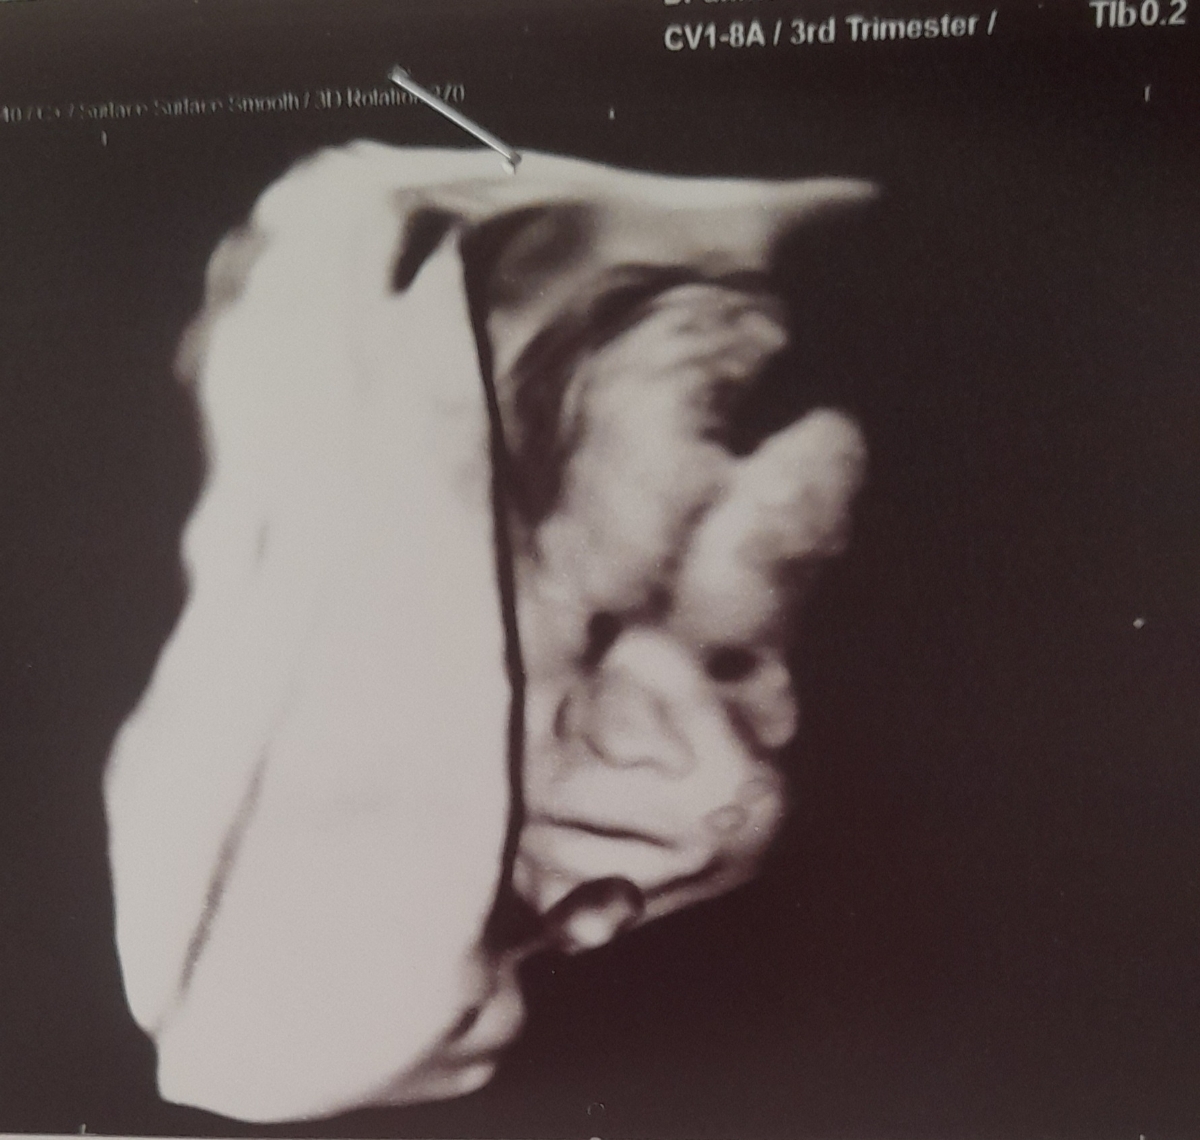

Parisa. h

اینم پسرمن😋😍

عکس سونوها رو خدا

خدا همه ی بچه ها رو حفظ کنه😍

آتنا صالحی

اینم قلقلی جون من 😍اگه روزشه مبارک